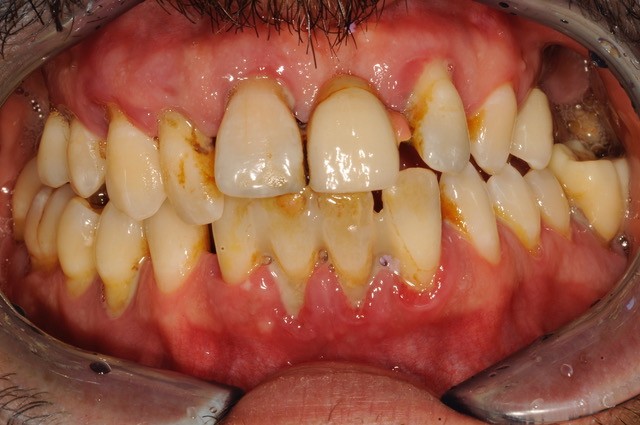

Situazione iniziale

Paziente molto giovane e cambio estetico molto importante, con altrettanto importante resettiva ossea del mascellare superiore.

Qui oltre all’indispensabile conoscenza e bravura chirurgica, brillantemente eseguita da Dott. Giuseppe Marano di Roma con il quale ho il piacere di collaborare e ringrazio per le immagini, c’è stato un profondo e attento progetto protesico in laboratorio.